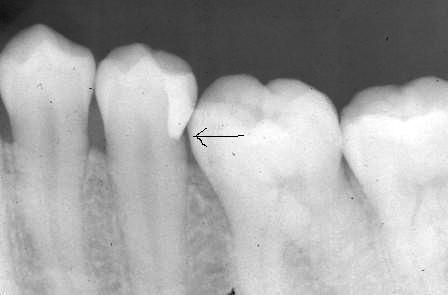

下顎7番の頬側歯茎部カリエスの原因 2025.06.04